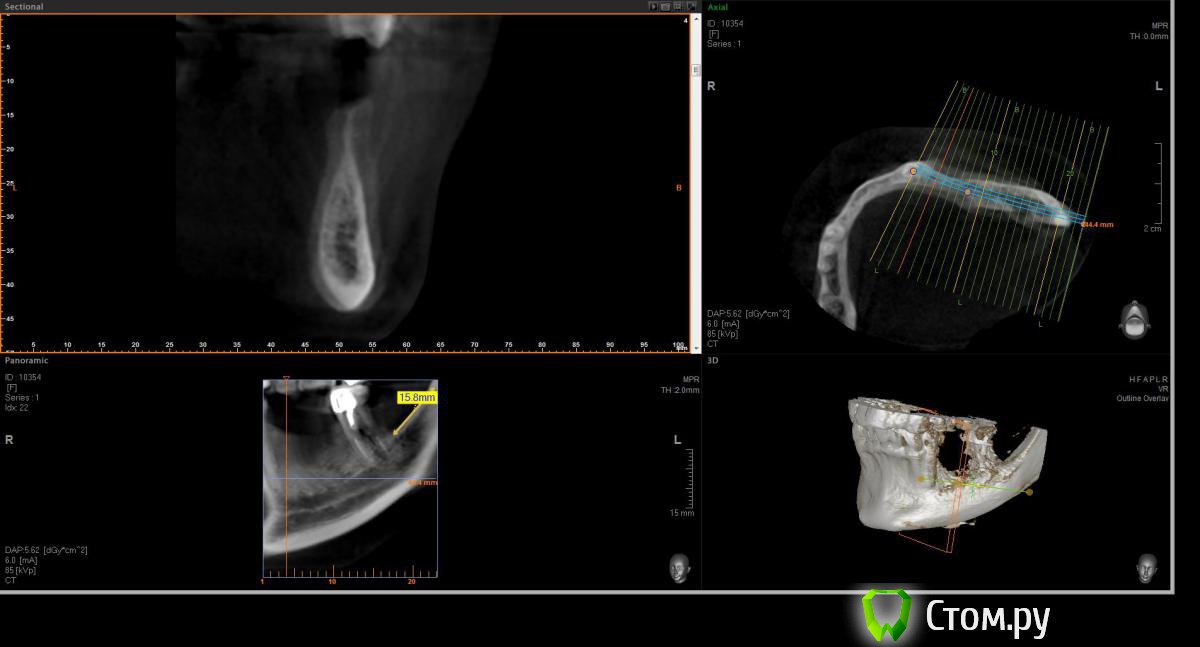

Opimar Опубликовано 21 июня, 2014 Поделиться Опубликовано 21 июня, 2014 Здравствуйте коллеги. Прошу вашей помощи и совета с пациенктой. В анамнезе травматичное удаление около 2-3 лет назад 35-36. Со слов пацинтки удалялось долотом и в 2 приема, вообщем по прошествию времени результат плачевный К мостовидному протезу пациентка не готова, очень хочет лечение с имплантантами и готова к костной пластике. Восстановить такой дефект ,если я правильно понимаю, более-менее прогнозируемо можно только с трансплантацией аутокостных блоков. Как раз по типу того как выкладывал Mane http://forum.stom.ru/topic/25799-kk-monokortikalnye-bloki/ либо по Кюри. Сам склоняюсь к забору блока с наружной косой линии или с подбородка. С блоками работать буду первый раз. Прослушал курсы Томаса Хансера. Прошу высазать идеи и предложения,возможны ли альтернативные методы? Кт прилагаю. Спасибо Ссылка на комментарий

Opimar Опубликовано 21 июня, 2014 Автор Поделиться Опубликовано 21 июня, 2014 Выкладываю еще. Пошагово от 34-37 Ссылка на комментарий

Bier Опубликовано 21 июня, 2014 Поделиться Опубликовано 21 июня, 2014 Выкладываю еще. Пошагово от 34-37темная точка достаточно высоко, это по моему не нерв, нерв ниже, я правильно понимаю? Ссылка на комментарий

Opimar Опубликовано 21 июня, 2014 Автор Поделиться Опубликовано 21 июня, 2014 темная точка достаточно высоко, это по моему не нерв, нерв ниже, я правильно понимаю?Да он ниже и язычнее. Провел от менталиса там еще запас есть. Ссылка на комментарий